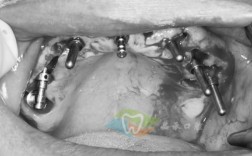

在技术特色上,昆山中医院牙科注重“数字化全程赋能”,术前通过CBCT获取三维口腔数据,结合口内扫描模型,在专业种植设计软件中模拟手术过程,制定个性化种植方案;术中利用数字化导板辅助,实现微创种植,手术切口通常仅需3-4mm,减少出血与术后肿胀;术后通过3D打印技术制作个性化牙冠,确保美观度与咬合功能高度匹配,科室还引入即刻种植、即刻负重等技术,对于符合条件的患者,可实现“当天种牙、当天戴冠”,缩短治疗周期,快速恢复口腔功能。

科室医生团队是种植牙服务的核心保障,团队成员均拥有口腔种植专业资质及多年临床经验,累计完成种植案例超万例,擅长处理复杂种植病例,如骨量严重不足、糖尿病等系统性疾病患者的种植修复,医生团队坚持“一人一方案”原则,结合患者年龄、口腔健康状况、骨密度等因素,综合评估种植风险与预期效果,确保方案的科学性与可行性,科室定期邀请国内外种植专家进行技术交流与学术研讨,紧跟国际前沿技术动态,不断提升诊疗水平。